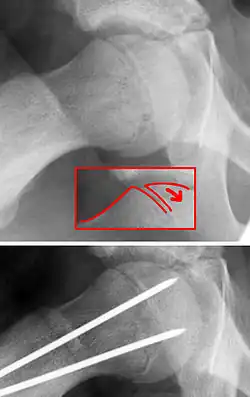

La epífisis desprendida,[1] epifisis femoral proximal deslizada,[2] deslizamiento epifisario de la cabeza de fémur,[3] o epífisis del capitel femoral deslizada (Slipped capital femoral epiphysis (SCFE) o skiffy en inglés), también coxa vara adolescentium, es un término médico que hace referencia a una fractura que atraviesa la placa de crecimiento (fisis) y que provoca el deslizamiento del extremo de la cabeza del fémur (metafisis) que se produce solo en niños y adolescentes.

De hecho, el término epífisis capitel femoral deslizada es una denominación inexacta, ya que la epífisis (parte final de un hueso) permanece en su posición anatómica normal en el acetábulo de la cadera. En realidad, lo que se desliza en sentido anterior con rotación externa es la metáfisis (parte del cuello del hueso).

La SCFE es una fractura Salter-Harris de tipo 1 a través del cartílago de crecimiento femoral proximal.[8]

La enfermedad SCFE, se puede tratar con clavos externos in situ o con clavos y reducción abiertos.[14]